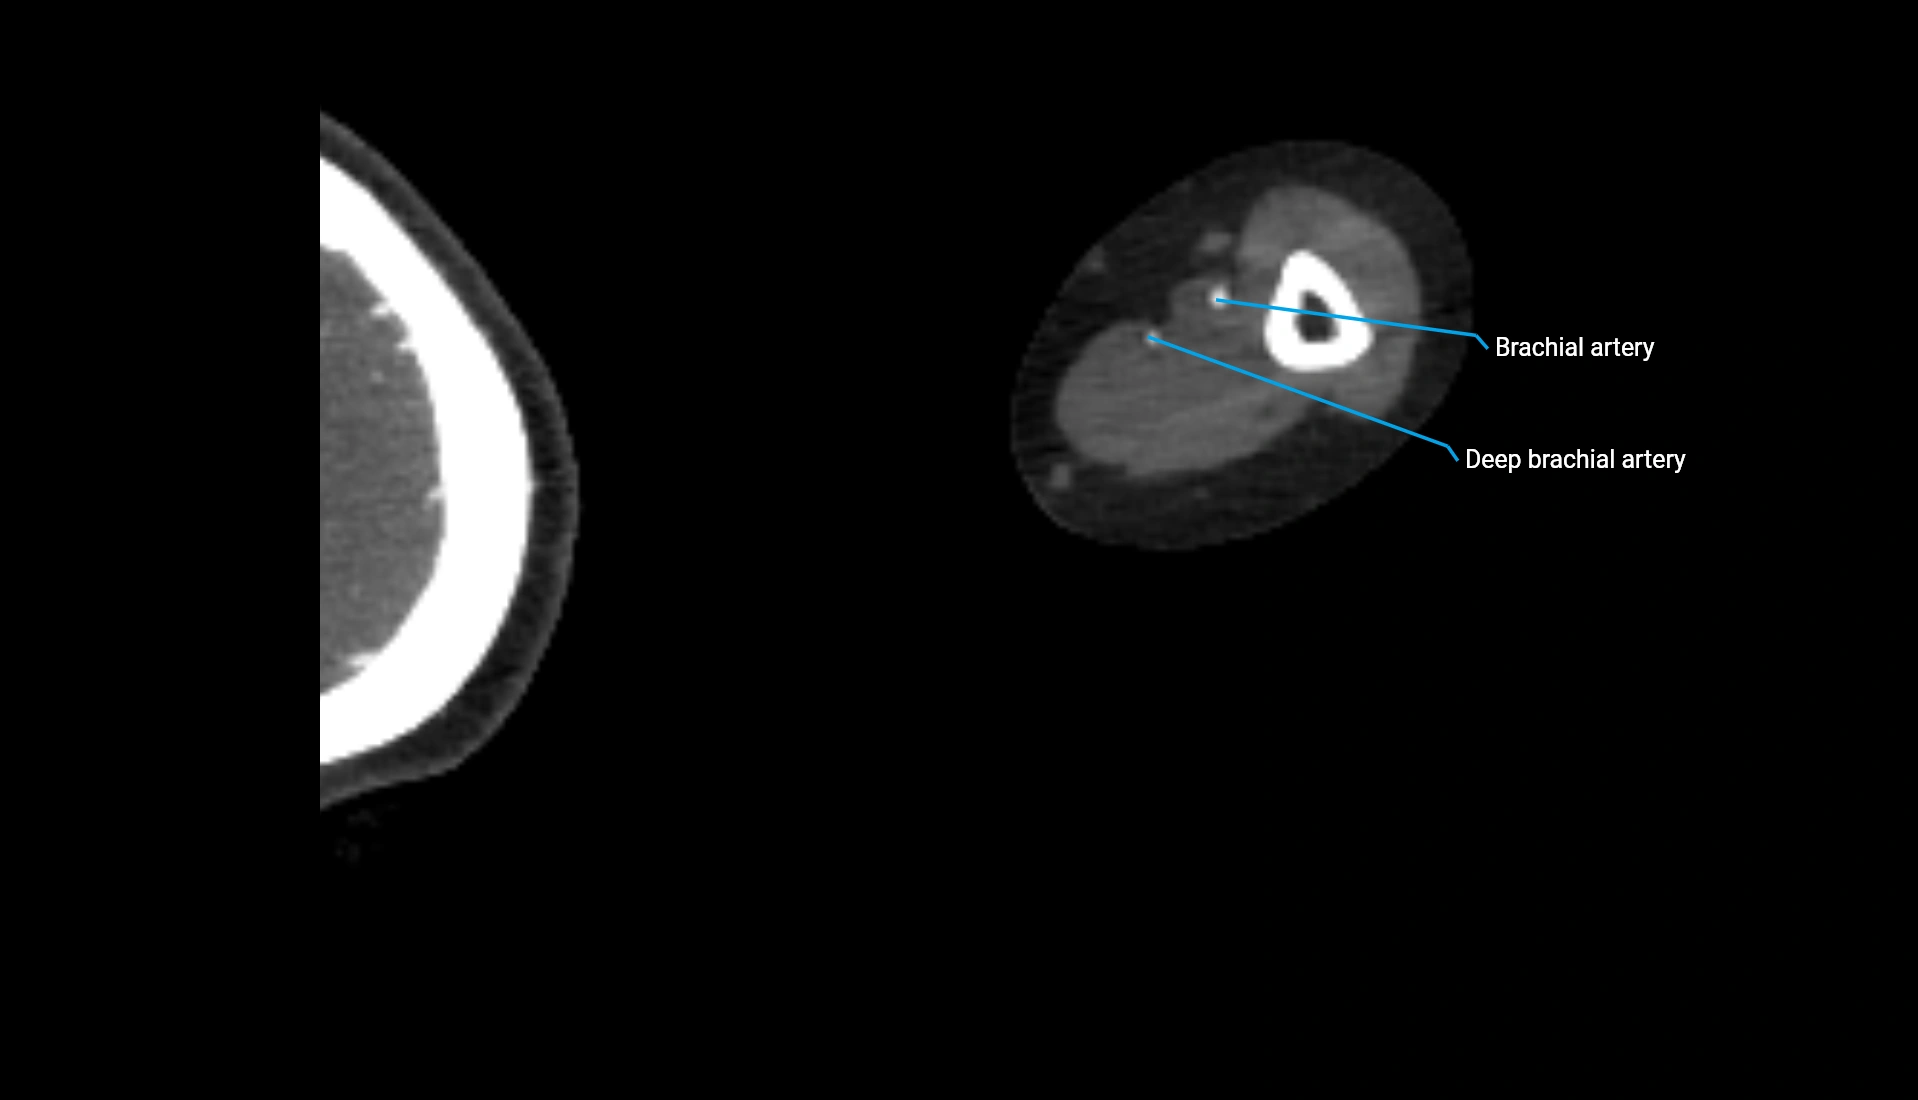

CT Appearance

Non-Contrast CT:

• Cortex: High-density, sharply defined

• Subchondral bone: Dense cancellous matrix

• Articular surface: Smooth concave contour articulating with the capitellum

• Excellent for evaluating bone integrity, alignment, and subtle fractures